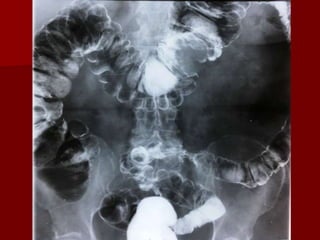

Ocluzie

intestinală